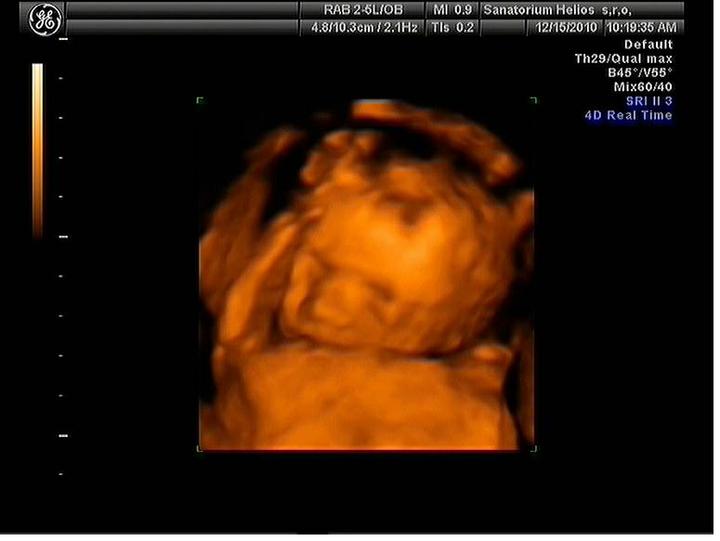

Jsme zpátky z dovolené, prcek v bříšku ani moc nezlobil🙂

Za 7 hodin uvidíme naši fazolku, nemůžu se dočkat a asi proto nemůžu spát. Strašně se těším. Snad bude vše v pořádku.